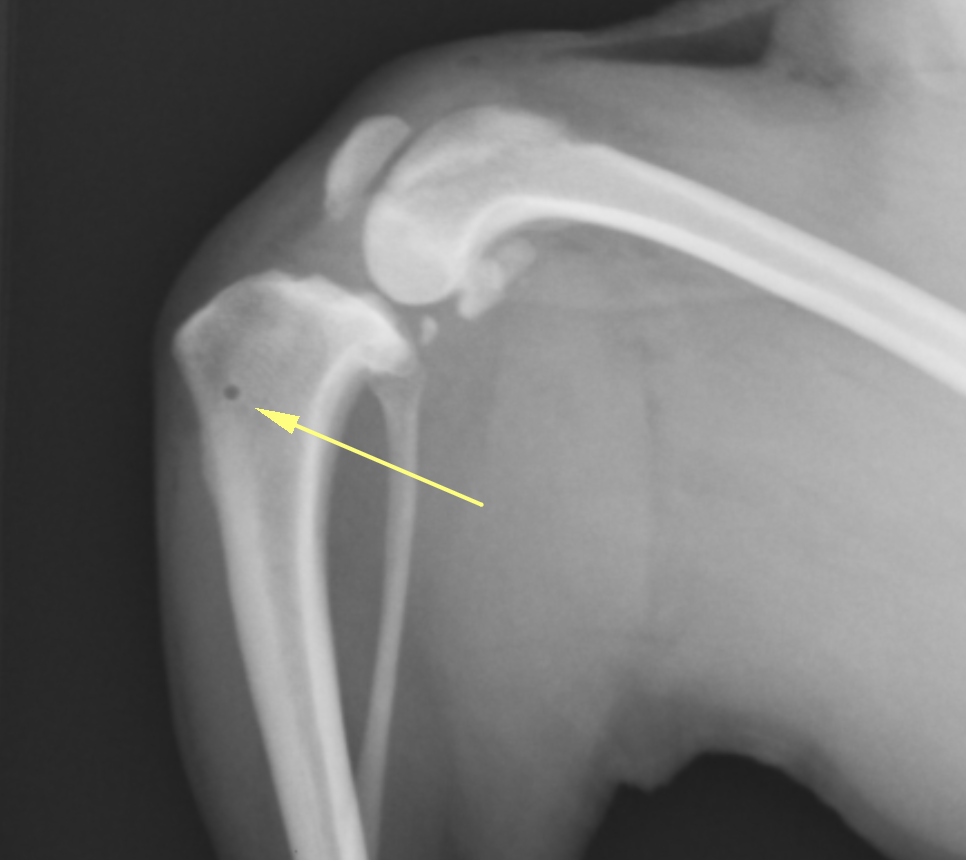

そのため、MPLグレード4の場合には手術の前にCT画像検査を実施し、大腿骨および脛骨と呼ばれる骨に変形がないかを確認します。レントゲンでも変形の評価はある程度可能ですが、3D的に変形していることが多いため、CT画像検査を実施しないと詳細がわからないことがほとんどです。

CT画像検査です。左のパテラ(向かって右側)は内側に大きく脱臼しています。この子の場合には大腿骨・脛骨共に大きな変形はないことがわかります。

膝蓋骨滑落防止スクリュー:大腿骨にスクリューを打ち、4頭筋を制御することでパテラを落ちないようにする方法です。